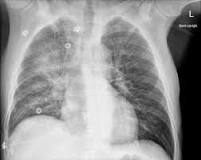

Bilateral air space opacification

• Diffuse air space opacification

• loss of silhouette sign

• air bronchograms

A

1. Cardiogenic

2. Non-cardiogenic